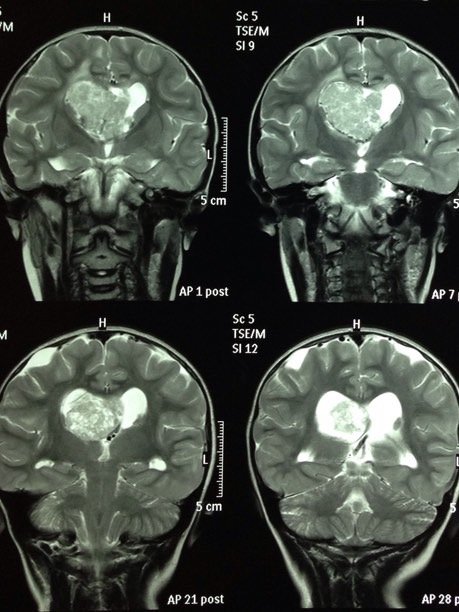

ESCLEROSIS TUBEROSA